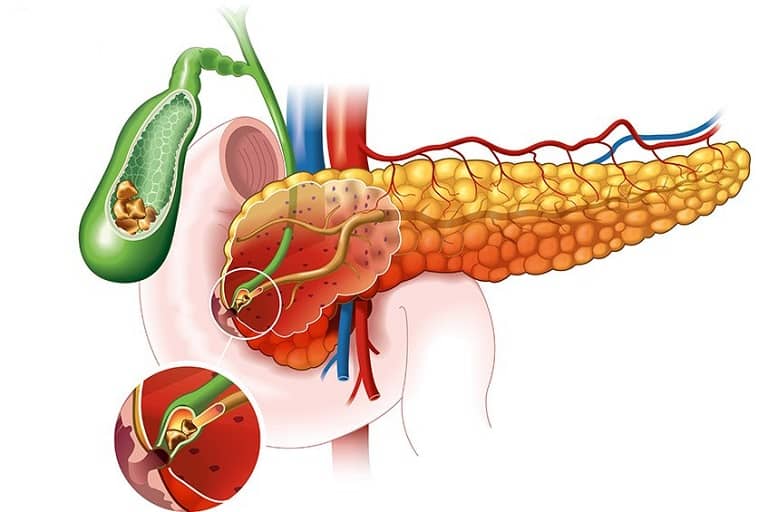

Hỗ trợ điều trị chữa sỏi mật, sỏi thận:

Một số bộ tộc thổ dân ở Nam Mỹ sử dụng DHC chữa sỏi mật và sỏi thận.

Một nghiên cứu của trường Đại học Dược Santa Catarina (Brazil-1984) đã phát hiện một alkaloid của Diệp hạ châu (phyllan thoside) có tác dụng chống co thắt cơ vân và cơ trơn, các nhà khoa học đã nhờ vào điều này để giải thích hiệu quả điều trị sỏi thận, sỏi mật của cây thuốc.